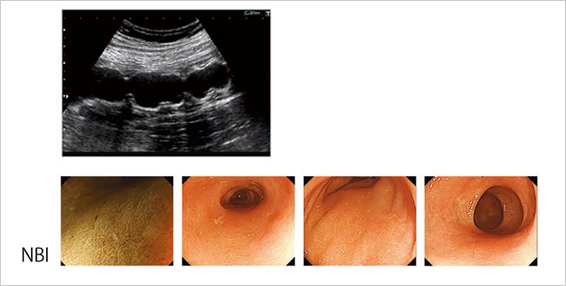

管腔内を自由に移動して観察する“Fly Thru”

従来の超音波の平行投影像に対して,Aplio500に搭載されたFly Thruは,透視投影法による3D画像を作成するアプリケーションである。管腔内から管腔壁を移動しながら観察する表示で,任意の観察方向にタッチパネルで簡単に操作できる。また,観察部位によっては方向を指示しなくても,Fly Thruが管腔を感知して,自動で誘導することも可能である。

図8は,43歳,女性で,潰瘍性大腸炎の症例である。小さなびらんが多発して認められ,慢性持続型・寛解期の内視鏡所見である。Fly Thruで下行結腸の粘膜面を確認すると比較的スムーズであり,内視鏡と同じく粘膜障害が少ない慢性持続型潰瘍性大腸炎との診断がついた。Fly Thruは,消化管領域では空気が存在し,超音波では描出しにくい問題もあるが,管腔であれば再構成が可能であり,今後のFly Thruの消化管への応用が期待される。

図8 43歳,女性,潰瘍性大腸炎のFly Thru画像